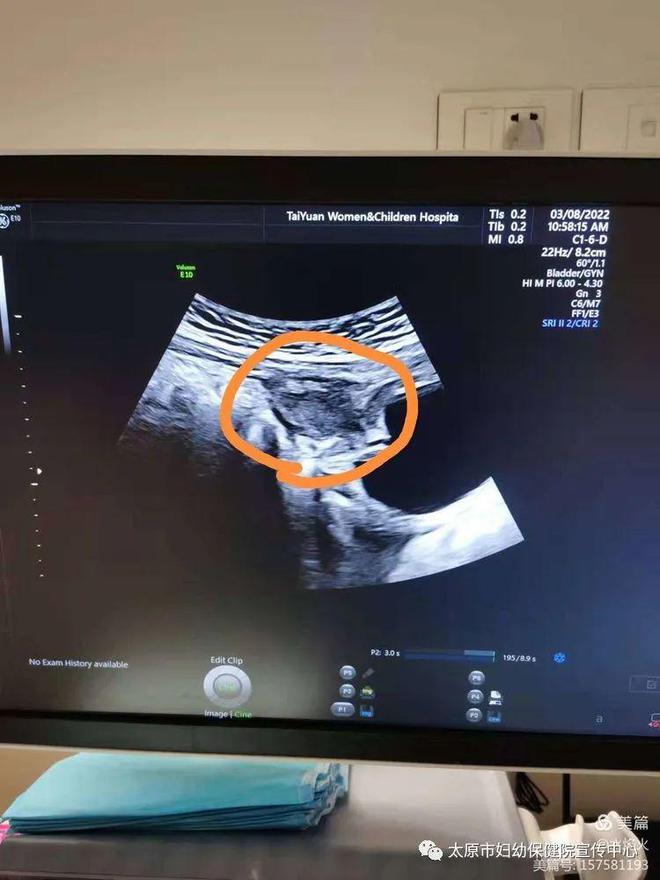

近日,太原市妇幼保健院儿外科成功完成一台腹腔镜下脐尿管囊肿切除术。患者是6岁的小女孩,因间断性腹部疼痛在当地医院检查,腹部彩超提示可能是脐尿管囊肿,随后来到市妇幼儿外科门诊就诊。CT检查后诊断为脐尿管囊肿合并感染,经抗菌药物控制感染后,给予手术治疗。

脐尿管囊肿是比较少见的泌尿系统先天性畸形疾病,表现为下腹正中的囊性包块,不随体位变动,位置表浅,与腹壁、膀胱关系密切。临床上易误诊,传统多采用开腹手术切除,但开放创伤大,脐部损毁大,术后恢复时间长,美体效果差,且患者接受度较低。

在术前准备过程中,外科主任郭瑞刚认真分析了病例的特点,反复确认了囊肿的位置,制定采用腹腔镜微创技术来完成手术。术前谈话时,患儿家属向医生表达了减少手术切口瘢痕的强烈意愿。经过2个多小时,手术圆满成功。术后,经过精心的护理,患儿已痊愈出院。